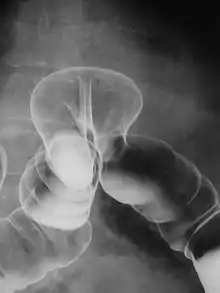

Lavement baryté en double contraste montrant une hernie transdiaphragmatique du côlon.

Un lavement baryté est un examen radiologique permettant d'étudier le rectum et le côlon.

Il consiste à injecter un produit de contraste opaque aux rayons X, la baryte, dans le rectum et le côlon du patient, via une petite canule introduite dans l'anus. Puis des clichés radiographiques de l'abdomen sont pris.